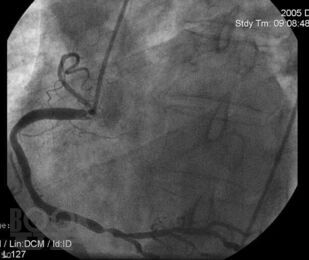

Chest Pain Syndrome

This textbook is developed in accordance with the Federal State Educational Standards of Higher Education (FSES HE) for the specialty 31.05.01 General Medicine (Moscow, 2020), the Basic Educational Program (BEP) for the specialty 31.05.01 General Medicine (2023), the curriculum (2023), and the course syllabus (2023) for students specializing in General Medicine. It is designed to facilitate the development of general professional competencies (GPC–4) and professional competencies (PC–5, PC–6) in accordance with the FSES.

This textbook presents modern knowledge of the basics of electrocardiography in cardiovascular diseases, necessary for students when studying the course «Propedeutics of Internal Diseases». The textbook also includes test tasks and situational problems of varying complexity for self assessment, with answer keys.